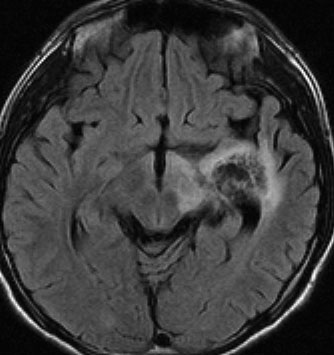

悪性神経膠腫と間違えそうなジャーミノーマ

14歳で右の片麻痺と学力の低下で発症しました。ガドリニウム造影がまだらで最初は膠芽腫かな?と思いましたが,mass effectが軽いことが解ります。geminomaとしては珍しいのですがperifocal edemaがあります。

定位生検術で病理組織診断をして化学療法を加えた後の画像です。germinomaのお約束どおり,化学療法できれいに消失します。ちょっとした小さな増強される部分が残るのですがこれはstromal reaction (gliofibrosis)をみているので,残存腫瘍ではありません。余分な追加の放射線治療をしないように気をつけます。